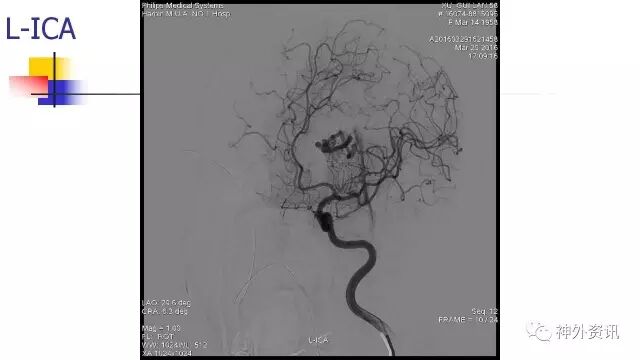

L-ICA正位动态

L-ICA动态